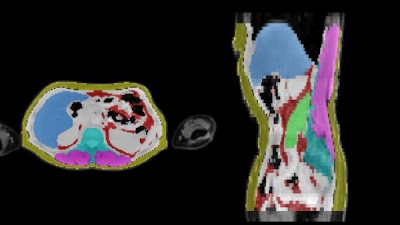

Evaluating Sex-specific Differences in Abdominal Fat Volume and Proton Density Fat Fraction on MRI Scans Using Automated nnU-Net-based Segmentation doi.org/10.1148/ryai.2… Mingming Wu BMRR #nnUNet #ML #MachineLearning

Evaluating Sex-specific Differences in Abdominal Fat Volume and Proton Density Fat Fraction on MRI Scans Using Automated nnU-Net-based Segmentation doi.org/10.1148/ryai.2… <a href="/MingmingWu10/">Mingming Wu</a> <a href="/BMRRgroup/">BMRR</a> #nnUNet #ML #MachineLearning